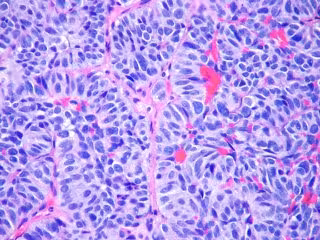

FLICKR/PULMONARY PATHOLOGY/ CC BY-SA 2.0